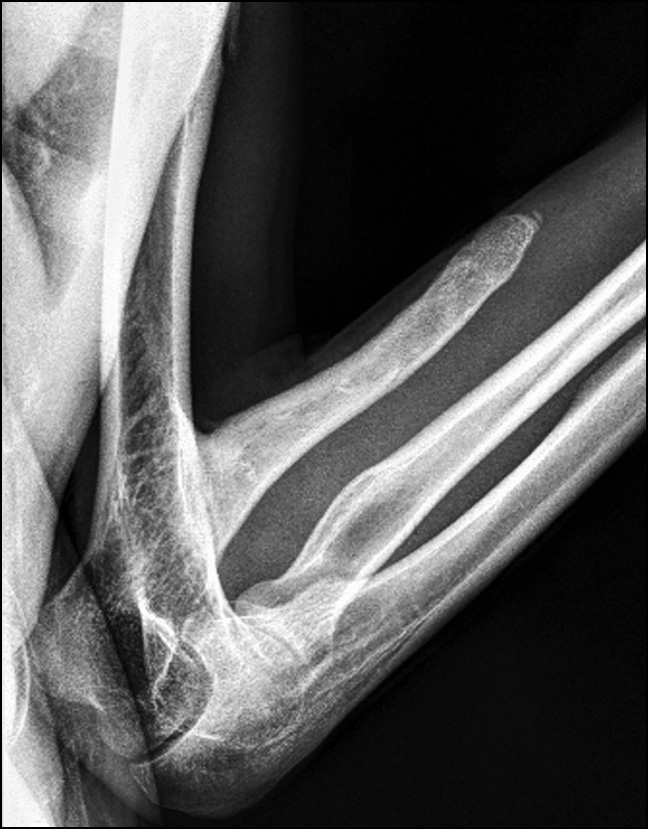

Control radiographs revealed multiple heterotopic ossifications of the axial and peripheral skeleton and submandibular region and multiplanar spinal deformity (Figs. 1–3). Computed tomography revealed synostosis of the 2nd–5th cervical vertebrae, which exhibited fusion of not only their posterior elements but also their bodies (Figs. 4 and 5). Synovial chondromatosis, one of the most common manifestations of FOP, was identified during a hip joint examination (Fig. 6). In addition to intra-articular chondromal bodies, heterotopic ossifications in the hip joints completely inhibit the movements in this skeletal region and significantly impeded walking (Figs. 7 and 8).

Fig. 1. Radiograph of the elbow joint: massive heterotopic ossification of the shoulder and forearm causing contracture of the elbow joint.